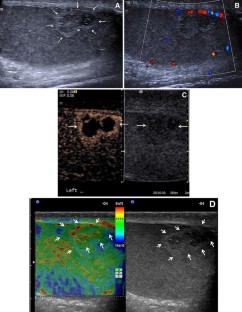

Fig. 1